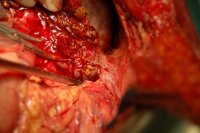

二、手术治疗[编辑 | 编辑源代码]

(1)可切除肝门部胆管癌手术方法的选择:

①肝门部胆管胆总管及胆囊切除胆肠吻合适用于未侵及肝实质之肝总管癌

②肝方叶或加部分右前叶切除及肝门部胆管肝外胆管切除胆肠吻合适用于肝总管癌或汇合部胆管癌

③肝方叶或左半肝切除及肝门部胆管肝外胆管切除胆肠吻合适用于左肝管及肝总管癌

④肝方叶或右半肝切除及肝门部胆管肝外胆管切除胆肠吻合适用于右肝管及肝总管癌

⑤超半肝或三肝切除及肝门部胆管肝外胆管部分尾状叶切除胆肠吻合适用于左或右肝管癌侵及二级以上肝管和尾状叶肝管

⑥姑息性切除肝方叶及肝门部胆管肝外胆管切除胆肠吻合并残留部分癌组织如尾状叶肝管或门静脉前壁

⑦门静脉主干汇合部或左右干前壁受侵犯者切除其受累部分静脉壁再予血管修补重建术后辅以腔内放疗

(2)肝门部胆管癌故息性手术:胆肠内引流术是首选的姑息手术方法原则是胆肠吻合口应尽量远离病灶根据PTC显示扩张的胆管情况选择胆肠吻合部位部分病例由于病灶侵犯肝门或因肝萎缩-肥大复合征存在萎缩叶胆管吻合引流价值不大肥大叶胆管显露困难使不少无法切除的病例仅能置管引流常用的方法是扩张癌性狭窄后放置尽可能粗而较硬的T形管U形管或内支撑导管T形管经胆总管或经肝引出